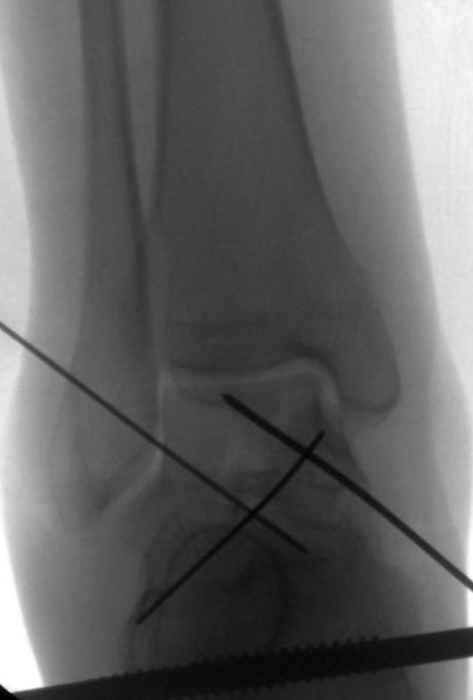

Вдогонку по поводу перелома таранной кости, больная 81, не страдает диабетом, перелом закрытый, в первый же день поступления ограничились временным наружным фиксатором (как на снимке).

Планировалась открытая фиксация после спадения отека, но больная пожелала лечиться по месту жительству в другом штате..

Из-за отека на стопе тактика лечения у всех была

одинаковая: временная наружная фиксация до спадения отека, при изолированных переломах они выписывались домой и через дней 7 госпитализировались на оперативное лечение.

Примеры на снимке...